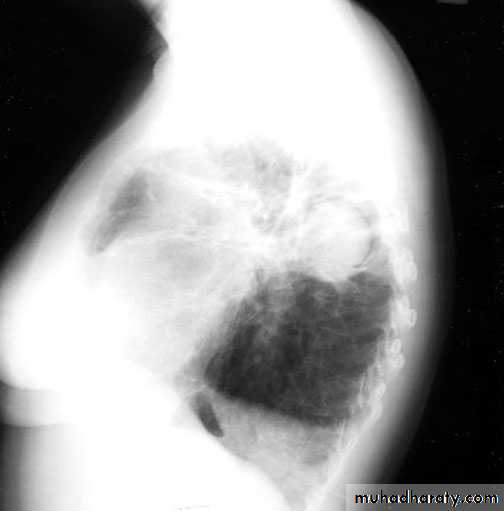

Tuberculoma mycetoma